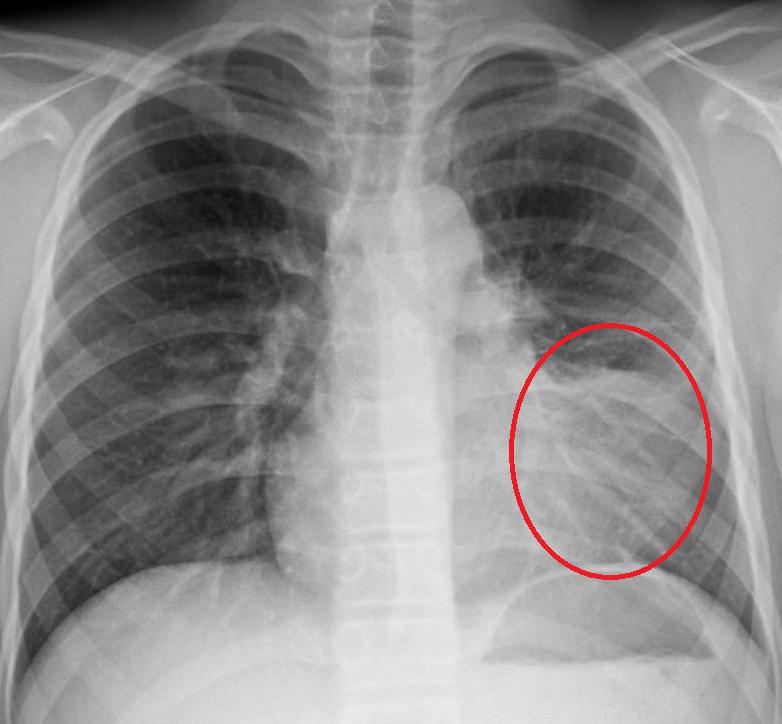

Правда ли, что пневмонию можно не услышать?

В.Ш.: К сожалению, это действительно так. Это несовершенство метода аускультации (лат. auscultatio — «выслушивание» — физический метод медицинской диагностики, заключающийся в выслушивании звуков, образующихся в процессе функционирования внутренних органов — прим. ред.). Некоторые небольшие пневмонии, особенно те, что располагаются не со стороны поверхности легких, а внутри, ближе к сердцу, действительно очень сложно услышать даже хорошему опытному врачу.

Правда ли, что обязательно нужен контрольный рентген?

В.Ш.: В классической форме пневмонии при амбулаторном лечении рентген не нужен. Тем более, как правило, рентгенологическое выздоровление запаздывает от клинического. Порой рентгенологическая инфильтрация может держаться месяц. Поэтому повторный рентген, выполненный через неделю, или через две, через три, может выявить инфильтрат, который, скорее всего, заставит врача назначить еще один антибиотик. И таким образом, пациент получит лишний курс антибиотиков, который в свою очередь, может пагубно сказаться на его здоровье.

Контрольный рентген нужен, только если у нас что-то идет не так. Если пациент не выздоравливает, мы не видим положительной динамики или нам не нравится течение болезни, тогда мы делаем рентген снимок.

Медицинские показания к проведению рентгенографии легких в двух проекциях (передняя, боковая) включают в себя подозрение на пневмонию при наличии следующих симптомов у пациента:

- Лихорадка выше 38°С с острым началом заболевания.

- Кашель с мокротой любого характера (от слизистой до гнойной с прожилками крови).

- Наличие аускультативных и перкуторных симптомов пневмонии: влажные хрипы, крепитация, укорочение тона.

- Изменения в общем анализе крови по типу лейкоцитоза с цифрами выше 10*109/л либо наличие палочкоядерного сдвига выше 10%.

При выявлении патологических изменений на рентген-снимке, характерных для пневмонии, пациенту назначается соответствующая терапия.

Как определить, что пневмония побеждена, если больной продолжает кашлять? Для этого необходимо сделать рентгеновский снимок легких. Иногда остаточные явления после пневмонии на рентгене наблюдаются как незначительные затемнения на легких. Их можно хорошо разглядеть на пленке.